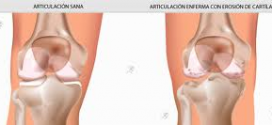

La artrosis de rodilla o gonartrosis. Es más frecuente en la mujer y suele presentarse a partir de los 50 años. Acostumbra ser bilateral, aunque la sintomatología puede predominar o incluso ser exclusiva de una rodilla. Afecta sobre todo el comportamiento femorotibial medial y la articulación femoropatelar. El genu varo y valgo son factores predisponentes para el desarrollo de una …

ARTROSIS

La artrosis es un proceso de localización articular, de instauración lenta y progresiva, que clínicamente se caracteriza por dolor y que en última instancia, cuando se trata de una articulación importante como la cadera o la rodilla, conduce a una impotencia funcional del miembro afectado. El elemento fundamental, desde el punto de vista de su patogenia, radica en que la …